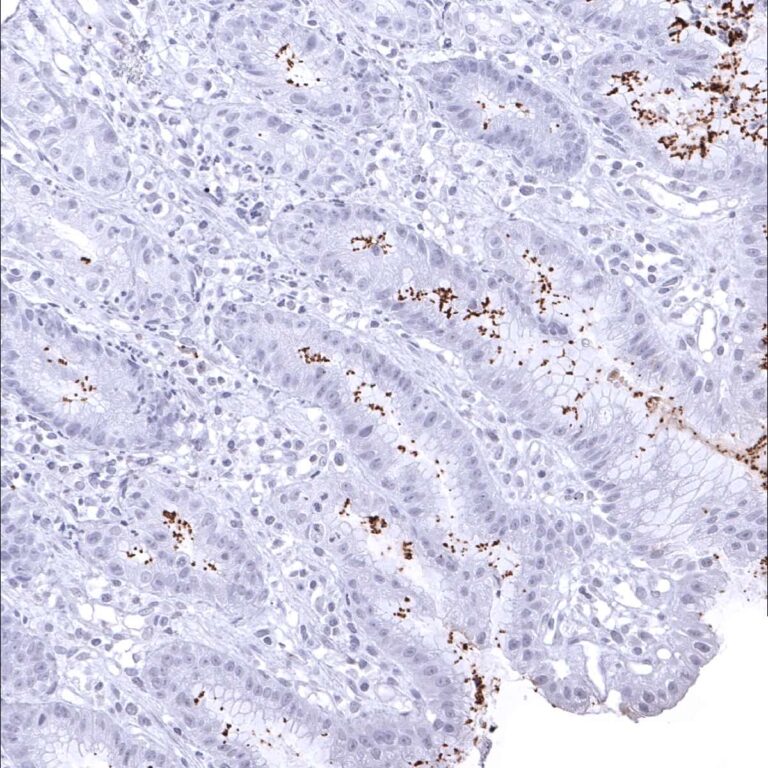

Positive control = Gastric tissue with known helicobacter pylori infection should show a distinct staining of bacteria on the surface and/or within glands.

Negative control = Gastric tissue: Normal epithelial and stromal cells should not stain.

Among normal adult tissues, immunostaining is not observed for the helicobacter specific antibody MSVA-466M.